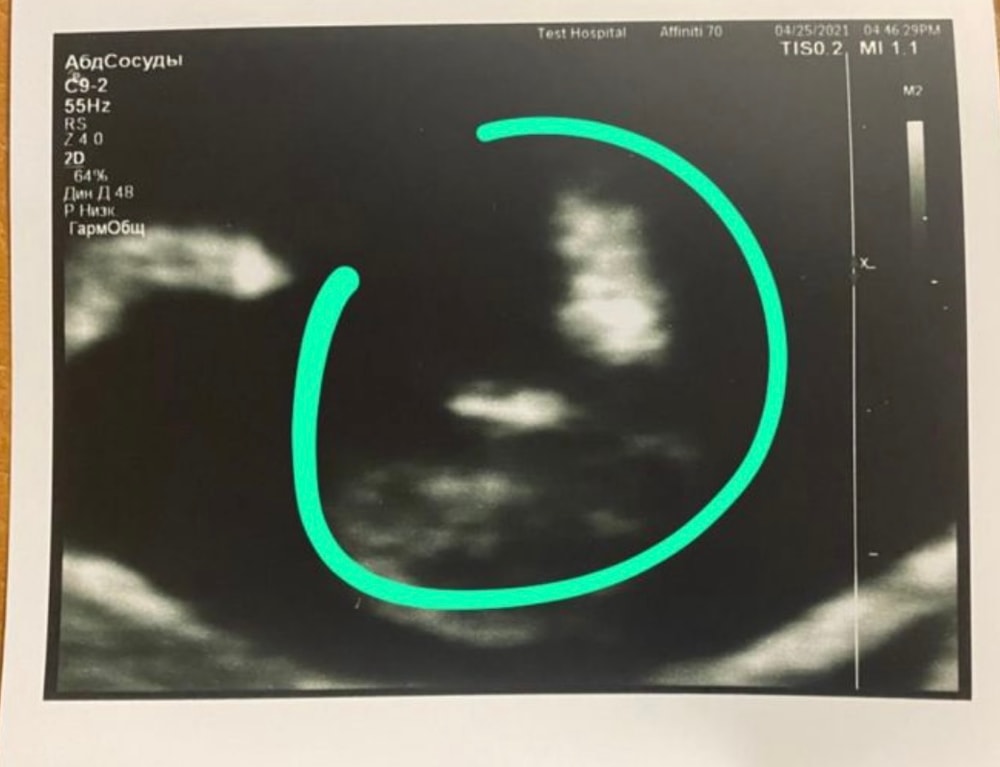

Мне одна и та же узист делала скрининги с тремя последними беременностями. В прошлые разы точно определяла мальчишек в 12 недель, причем смотрела не сбоку половой бугорок, а именно между ножек. Я думала тогда что она просто угадала. И в этот раз она так же между ножек смотрела, и сказала что ничего мальчишеского не видит, что скорее всего девочка. Я конечно не поверила, ну думаю как можно на таком сроке что то между ножек разглядеть, когда в статьях пишут что на этом сроке у них там все якобы одинаково. Но позже нам подтвердили девочку, и на узи, и по НИПТу. Вот фото третьего сына между ножек: Изображение А вот у дочки на таком же сроке 12 недель: Изображение